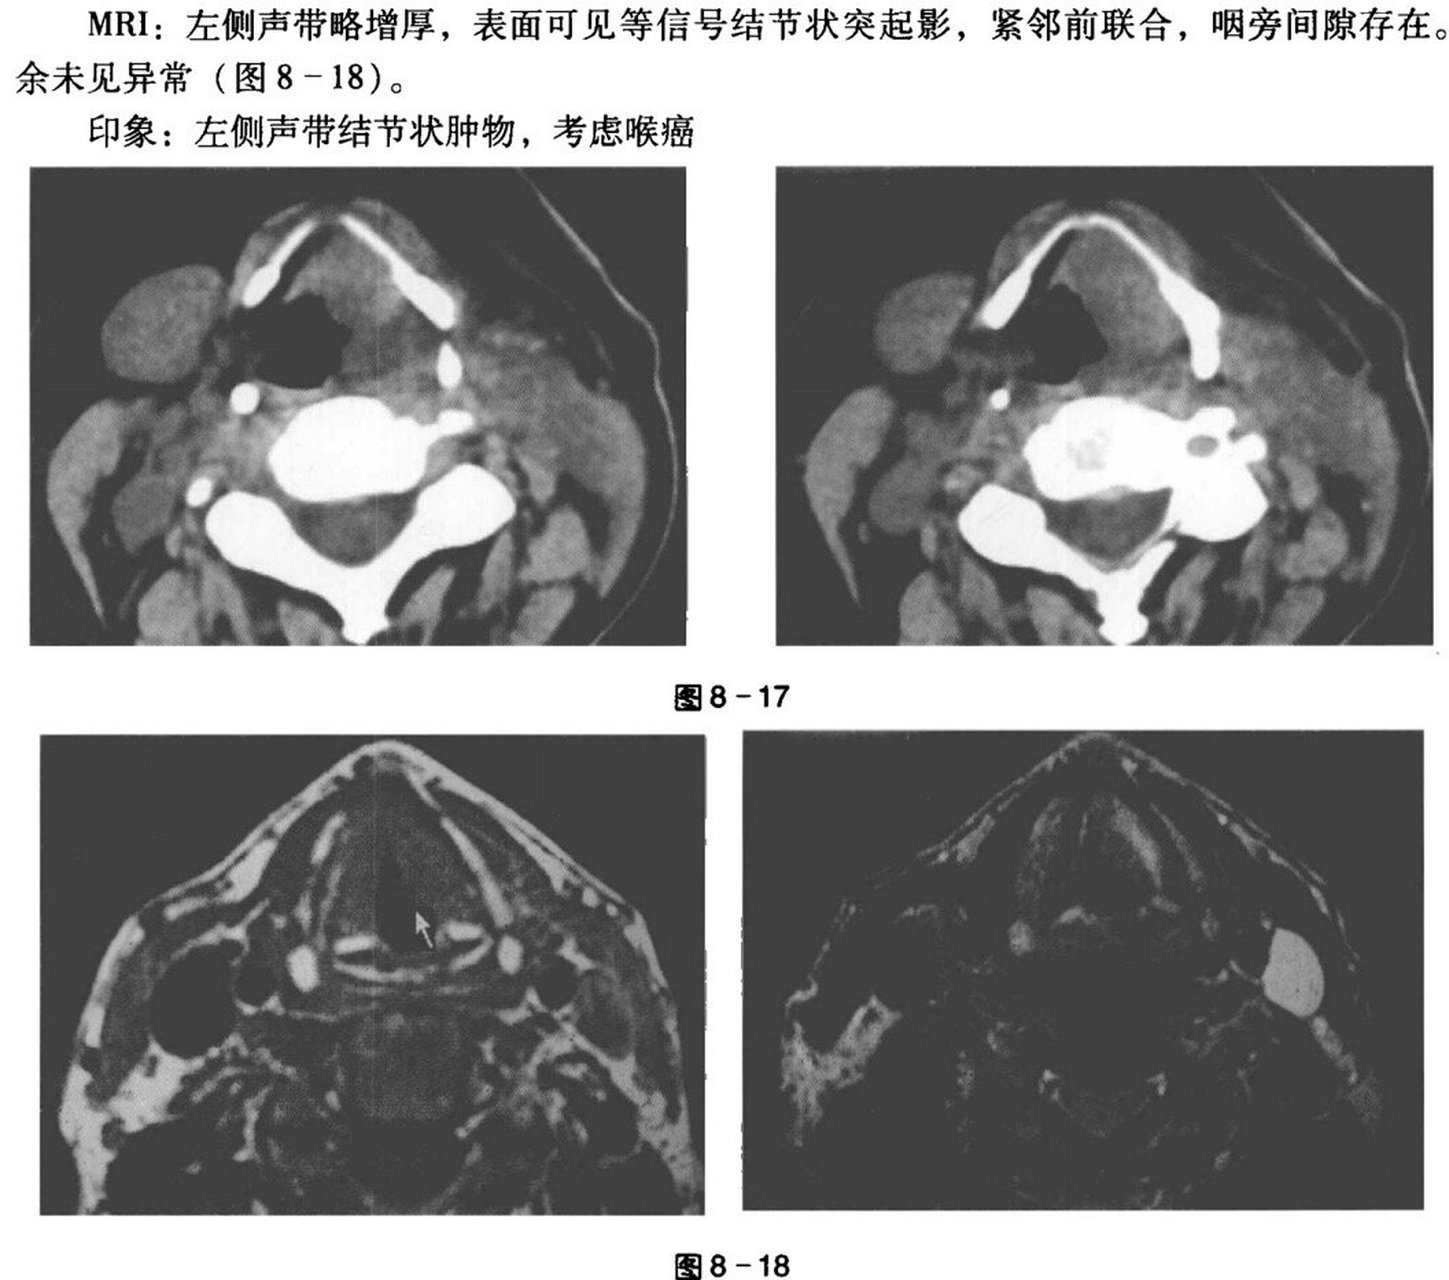

喉癌的ct,mri诊断